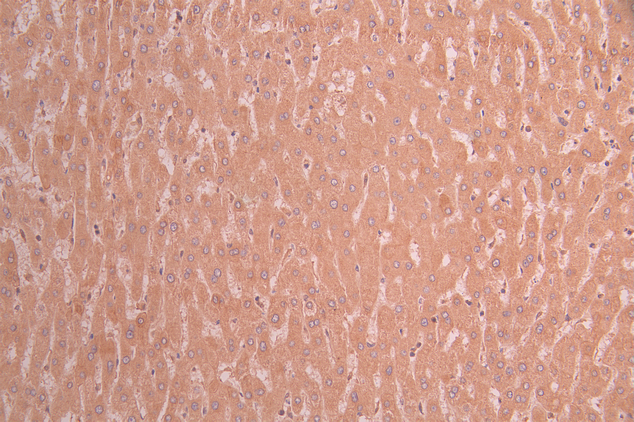

IHC image of CSB-RA143705A0HU diluted at 1:100 and staining in paraffin-embedded human liver cancer performed on a Leica BondTM system. After dewaxing and hydration, antigen retrieval was mediated by high pressure in a citrate buffer (pH 6.0). Section was blocked with 10% normal goat serum 30min at RT. Then primary antibody (1% BSA) was incubated at 4°C overnight. The primary is detected by a Goat anti-rabbit polymer IgG labeled by HRP and visualized using 0.05% DAB.